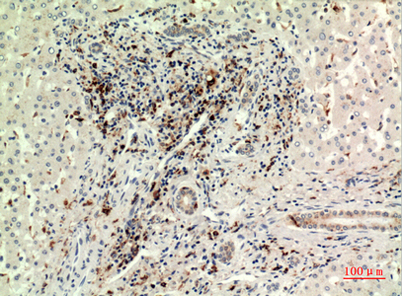

Product name: CD74 rabbit pAb

Dilutions: Western Blot: 1/500 - 1/2000. IHC-p: 1/100-1/300. ELISA: 1/20000. Not yet tested in other applications.

Immunogen: The antiserum was produced against synthesized peptide derived from the Internal region of human CD74. AA range:161-210